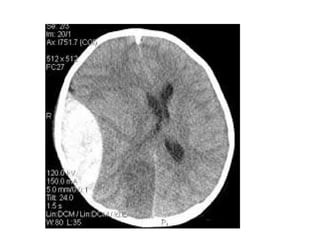

NECT shows hyperdense internal veins and bilateral (R > L) thalami

hypodensities , compatible with dural vein thrombosis and venous